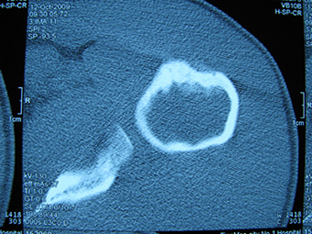

标题: X6404B:肱骨骨质破坏(CT片) [打印本页]

标题: X6404B:肱骨骨质破坏(CT片)

男,50岁,左肩部轻微疼痛,活动不便5个月就诊,近十天加重,无红肿热,间断理疗治疗无好转,既往5个月前左肩轻微拉伤史

骨巨?动脉瘤样骨囊肿?

内生软骨瘤。

内生软骨瘤。

内生软骨瘤?-----------

年纪大了,先要排除转移瘤。

髓腔内软组织肿块并斑片状钙化,考虑高分化软骨肉瘤可能性大。

考虑骨巨或动脉瘤样骨囊肿。

内生软骨瘤可能性大,期待结果。

孤立性骨囊肿。

内生软骨瘤可能性大

其内可见钙化,考虑软骨源性肿瘤,内生软骨瘤可能

但由于年龄较大,恶性软骨肉瘤待排

肱骨头内巨大软组织肿块并斑片状钙化,内生软骨瘤?骨巨细胞瘤?软骨粘液样纤维瘤?期待结果!

髓腔内软组织肿块并斑片状钙化,考虑高分化软骨肉瘤可能性大。

内生软骨瘤可能性大

肱骨头内巨大软组织肿块并斑片状钙化,内生软骨瘤?骨巨细胞瘤?软骨粘液样纤维瘤?期待结果

考虑内生软骨瘤?骨巨细胞瘤?

内生软骨瘤?骨巨细胞瘤?

先要排除转移瘤。